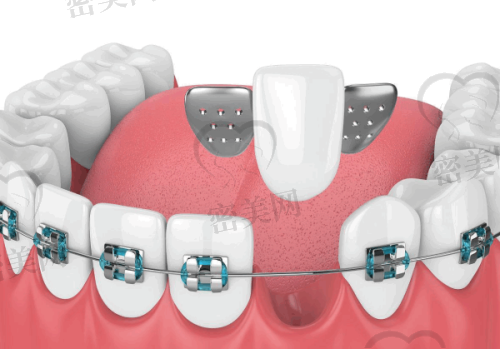

王安文院长:擅长复杂类牙齿种植技术,如穿颧穿翼种植术及全口种植(All-on-4)。

特色诊疗服务涵盖:All-on-4种植、数字化种植导航、陶瓷贴面微笑设计、儿童行为管理下齿科治疗等。